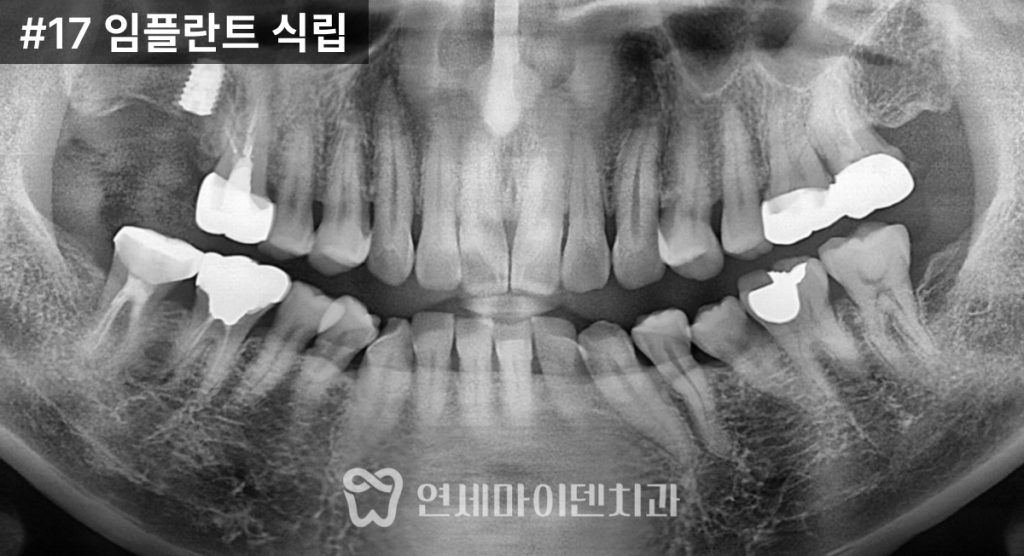

발치된 17번 어금니 부위는

뼈의 높이가 전반적으로 낮아져 있었습니다.CT 분석 결과,

상악동 바닥이 아래로 내려와 있었고

점막도 다소 두꺼워진 상태였습니다.이러한 상황에서

임플란트를 단순 식립할 경우

상악동 내부를 침범할 위험이 있어

상악동 거상술을 동반한 임플란트 식립이

필요했습니다.

얇아진 상악동 점막이 손상되지 않도록

미세기구를 이용해

상악동 바닥을 조심스럽게 들어 올렸고,

그 공간에 소량의 뼈이식재를 채운 뒤

임플란트를 식립했습니다.이식된 뼈 아래에는

단단한 치조골이 남아 있었기 때문에,

해당 부위를 이용해

임플란트의 초기 고정력을

확보할 수 있었습니다.

수술 직후에도

염증 악화나 부비동 통증 없이

안정적으로 회복되었고,

잇몸이 충분히 아문 후

2차 수술을 진행했습니다.이후 맞춤형 지대주를 연결하고

최종 보철물을 제작해

저작 기능을 회복했습니다.치료 결과와 경과

치료 후 CT와 임상 사진에서

임플란트의 안정적인 고정 상태와

교합 회복을 확인할 수 있었습니다.앞쪽 16번 치아는

신경치료 후

2년 이상 안정적으로 유지되고 있으며,뒤쪽 17번 임플란트 역시

상악동염 재발 없이

건강하게 기능하고 있습니다.상악동염이 있어도 임플란트가 가능한 이유